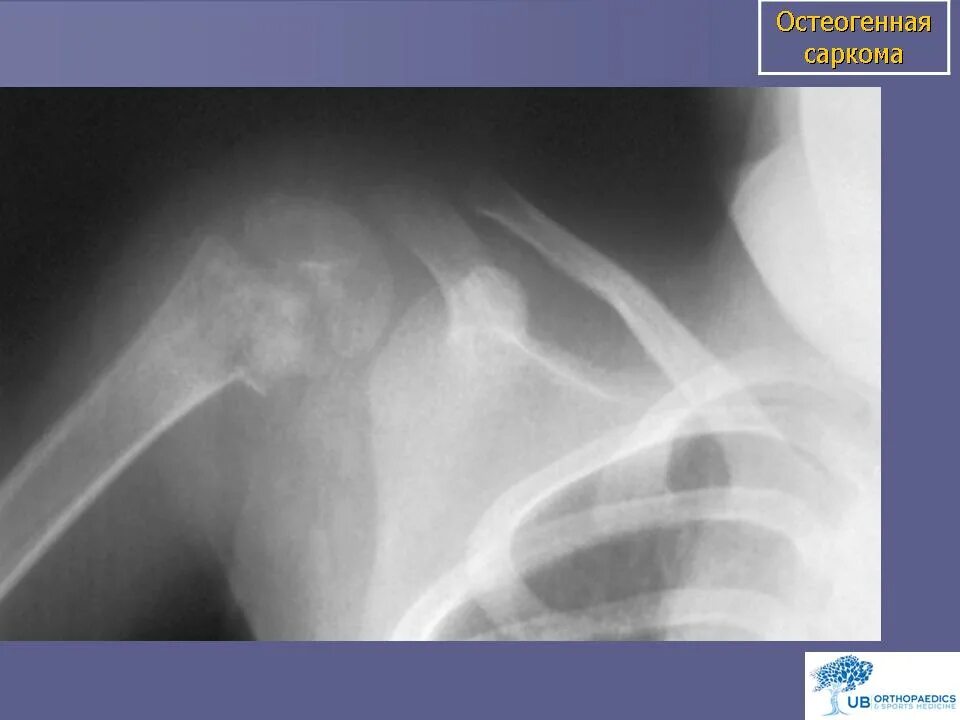

Метастазы в ключице